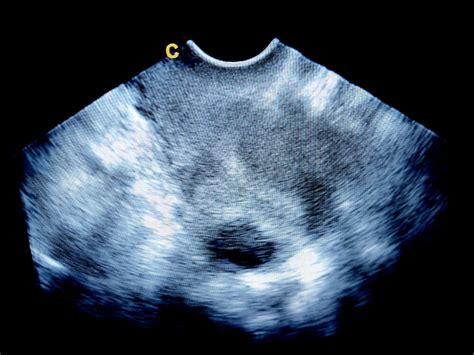

Najpomembnejša diagnostična preiskava za potrditev pregrade maternice je nožnični ultrazvok. Če ginekolog s pomočjo ultrazvoka ne more postaviti dokončne diagnoze, se lahko odloči za dodatne preiskave, kot sta histeroskopija ali laparoskopija. Histeroskopija omogoča neposredno vizualizacijo notranjosti maternice, medtem ko laparoskopija omogoča pregled zunanjosti maternice in medeničnih organov.